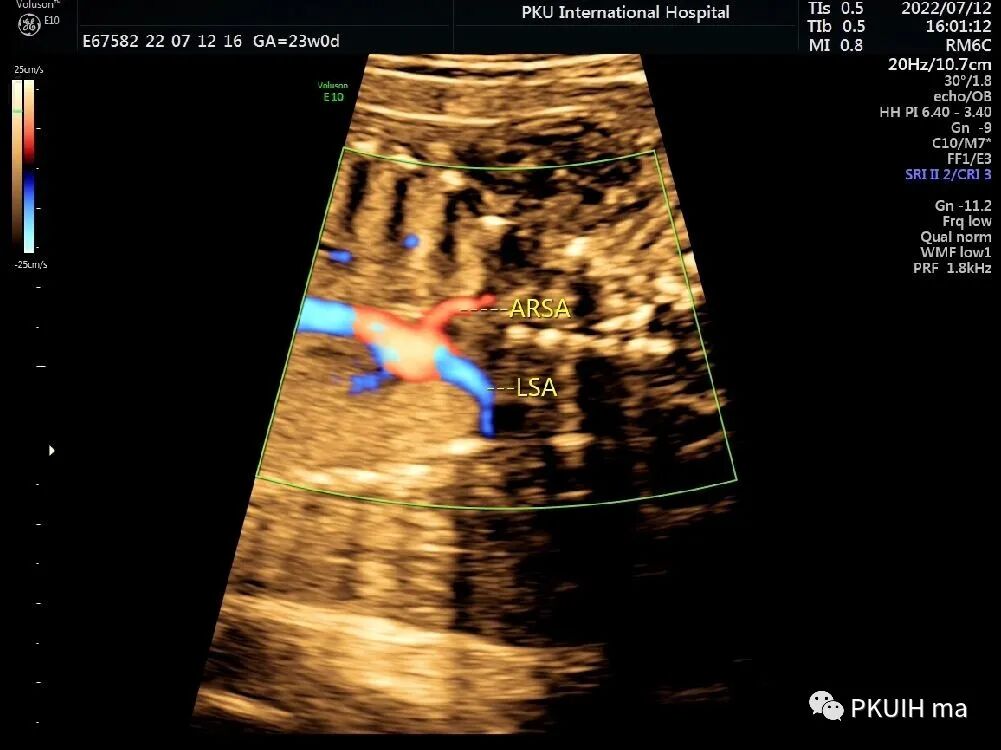

冠状切面显示右锁骨下动脉起于主动脉弓降部(ARSA:迷走的右锁骨下动脉,LSA:左锁骨下动脉)

ARSA较多见,常认为是一种正常的变异。超声很容易诊断,观察时建议把血流标尺降到15-20cm/s,也可以采用三维超声多平面观察或四维血流显像模式辨认。发现右锁骨下动脉迷走时建议做心内外系统全面扫查。单纯的锁骨下动脉迷走如果不合并染色体异常一般无临床意义,出生后预后良好。由于单纯锁骨下动脉迷走不形成完整血管环,临床上常无明显症状,仅有极少数病例报道患儿有吞咽困难或呼吸困难。迷走的右锁骨下动脉还可能会压迫喉返神经,导致神经麻痹,这种情况称为 Ortner 综合症。因此,临床中发现锁骨下动脉迷走时要注意观察迷走的血管与气管和食管的关系,食管后型最常见(80%),其次是气管、食管间型(15%),最后是气管前型(5%)。ARSA合并21-三体有文献报道,同时ARSA也出现在其他一些染色体非整倍体异常中;同时ARSA也可合并一些心脏的锥干畸形,此时要注意22q11微缺失的染色体异常风险。